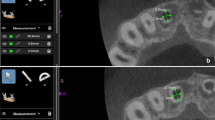

Periapical X-ray images of tooth roots were acquired by using a X-ray clinical apparatus (Corix 70 Plus KVP X-ray™, CORAMEX S.A, Mexico). X-ray analyses were performed on triangular scanning technique at 70 kVp and 8 mA for 53 s [36]. As seen in Fig. 2, cone beam computed tomography (CBCT) was performed to measure the tooth root canals’ diameter, remnant dentin thickness, and the endodontic post to dentin distance. The CBCT unit KaVo OP 3D™ (KAVO, Germany) used in this study operates in different set up, expanding from panoramic-only through cephalometric, and three-dimensional capabilities to accomplish three-in-one configuration.

The CBCT focal spot was at 0.5 mm, IEC 336 (IEC 60336/2005) while the tube voltage and the tube current were set at 60–95 kV and 3.2–16 mA, respectively. Image voxel size ranged from 80 up to 400 μm and the scanning was performed for 27–45 s. A fast scan time was provided by the complementary metal-oxide semiconductor (CMOS) X-ray detectors. The image volume sizes (H × Ø) were the following: 5 × 5, 6 × 9, 9 × 11, and 9 × 14 cm. Different resolution levels could be evaluated such as: low dose technology scan, standard resolution scan, high resolution scan, and endo resolution scan. CBCT was coupled to the Blue Sky Plan 4™ software program (BlueSkyBio, USA). Two hundred and seventy-five axial cross-sectioned CBCT images were acquired for each tooth root specimen. Cross-sections were evaluated at each tooth root third: coronal, middle, and apex. Tooth root canal diameter was measured prior to the placement of the GFRC post (Fig. 2B). Then, the GFRC post to dentin distance was measured at mesial, distal, buccal, and lingual regions. Navigation and evaluation of the anatomical details was supported by the Blue Sky Plan software as previously reported in literature [37, 38].

As seen in Fig. 3, CBCT images revealed differences in diameter at different thirds of the tooth root canal prior to the placement of the endodontic post (Fig. 2B). The endodontic post to dentin distance was measured at mesial, distal, buccal, and lingual regions. The mean values and standard deviation values recorded for tooth remnant thickness are shown in Fig. 4. On mesial and distal regions, invasive preparation revealed the lowest values of remnant tooth tissues at the three thirds (coronal, middle, and apex) compared to the standard preparation and minimally-invasive (conservative) sha**. At mesial side, the mean values of remaining tooth thickness at the coronal third were recorded at 1.63, while mean values of 1.49 and 1.21 mm were recorded at middle and apical thirds, respectively (Fig. 4A). Results showed statistically significant differences regarding the invasive sha** (p < 0.05). At the distal level, the mean values of remaining tooth thickness were recorded at 1.72, 1.46, and 1.45 mm, at coronal, middle, and apical thirds, respectively (Fig. 4B). Thus, thickness of the remnant tooth tissues decreased from the coronal to the apex third region.

CBCT images of the GFRC post to dentin after invasive sha** of the tooth root canal are shown in Fig. 7A and C. The distance from the GFRC post to the remaining dentin was much more uniformly than at the coronal level. Microscopic images of the interfaces involving dentin, resin-matrix cement, and GFRC post can be seen in Fig. 7B and D and Fig. 8. As seen in Fig. 7A and B, the invasive tooth preparation promoted a larger destruction of tooth root inner tissues as noticeable by the space from the GFRC post to the intracanal dentin surfaces. Results showed statistically significant differences between groups (p < 0.05). The space was filled by the resin-matrix cement although macro-scale voids were detected (Fig. 7B and D). In Fig. 7C, the post was fitted in the apex third region that decrease the resin-matrix cement layer as seen by the optical microscopy analysis (Fig. 7D and 8).

CBCT and microstructural images of the GFRC post to dentin distance on invasive sha**. CBCT images of a A coronal and C sagittal cross-section plane of the tooth with a GFRC post prior to cementation: zoom view of A coronal and C apical tooth third. B Optical microscopy of a horizontal cross-section of the GFRC post to dentin interface at the B coronal and D apical third after cementation